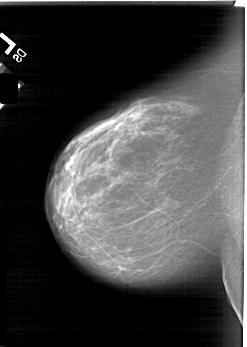

A_1813_1.RIGHT_MLO

RIGHT_MLO LINES 6736 PIXELS_PER_LINE 3976 BITS_PER_PIXEL 12 RESOLUTION 43.5 OVERLAY